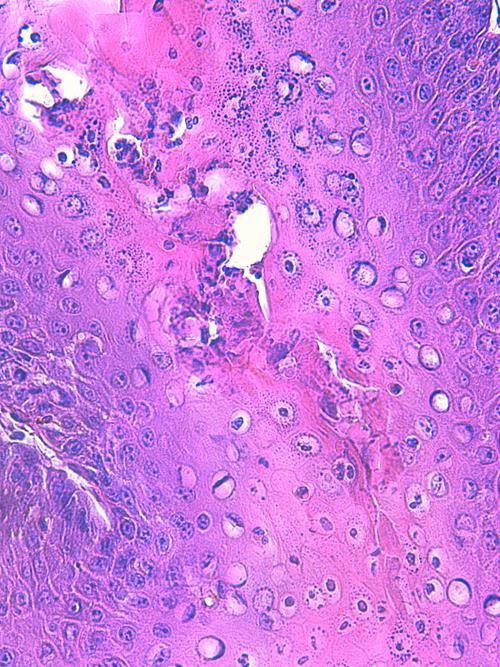

Photo 4 (Hémalun-Eosine X200) peau velue : Vue rapprochée de la Photo 3 montrant

la zone de fissuration de la gaine épithéliale externe d’un infundibula folliculaire avec lyse des

attaches desmosomiales intercellulaires et afflux de granulocytes éosinophiles donnant

naissance à des micro-pustules pariétales multiloculaires.

Légendes de la Photo 4 :

- Double flèche verte : grand axe de l’infundibulum folliculaire

- Double flèche rose : épiderme

- Flèches jaunes : fissuration de la gaine épithéliale externe avec lyse des attaches desmosomiales intercellulaires et afflux de granulocytes éosinophiles

- Ronds marrons : parakératose

- Étoiles rouges : micro-pustules pariétales multiloculaires (folliculite murale) et luminales obstruant l’abouchement folliculaire

- Étoiles turquoises : à gauche infiltrat inflammatoire dermique (au milieu en bas, erreur)

- Étoile vertes : orthokératose